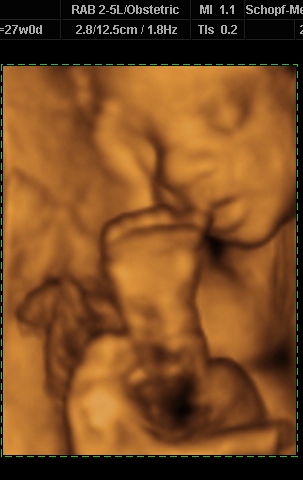

Ugye most vagyok a 29. hét elején. Babuba 1700 (!)

gramm, a doki azt mondta, gyönyörűen fejlődik, egészséges, minden oké.

A 32 hetes babák vannak 1600 gramm körül.

Ja, és mivel 31 hetesnek mondanak, a mai UH szerint a szülés várható időpontja: augusztus 31.